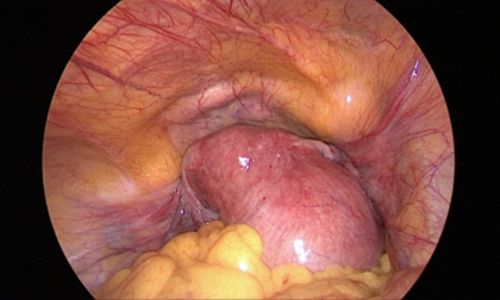

Photo showing a large fibroid in the fundus and body of the uterus:

During surgery, no incisions were made on the abdominal wall. The procedure was performed through the natural birth passage using a hysteroscope, which allowed direct visualisation of the uterine cavity. The fibroid was identified & removed using an energy source.